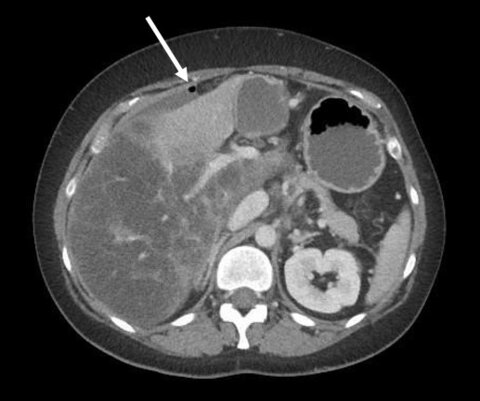

A 38-year old female presented to the emergency department with a one-day history of acute pain in the upper right quadrant of the abdomen, increasing within the last few hours. Her medical history included a non-alcoholic fatty liver disease with moderate hepatic fibrosis, endometriosis and hypertension.